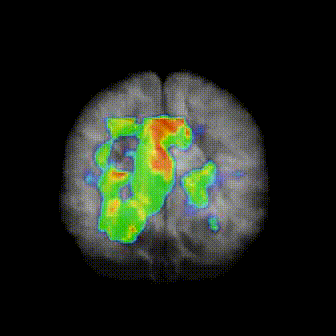

His work focused on pioneering functional neuroimaging methods for studying sleep and the development of novel brain based interventions for the treatment of neuropsychiatric and sleep disorders.